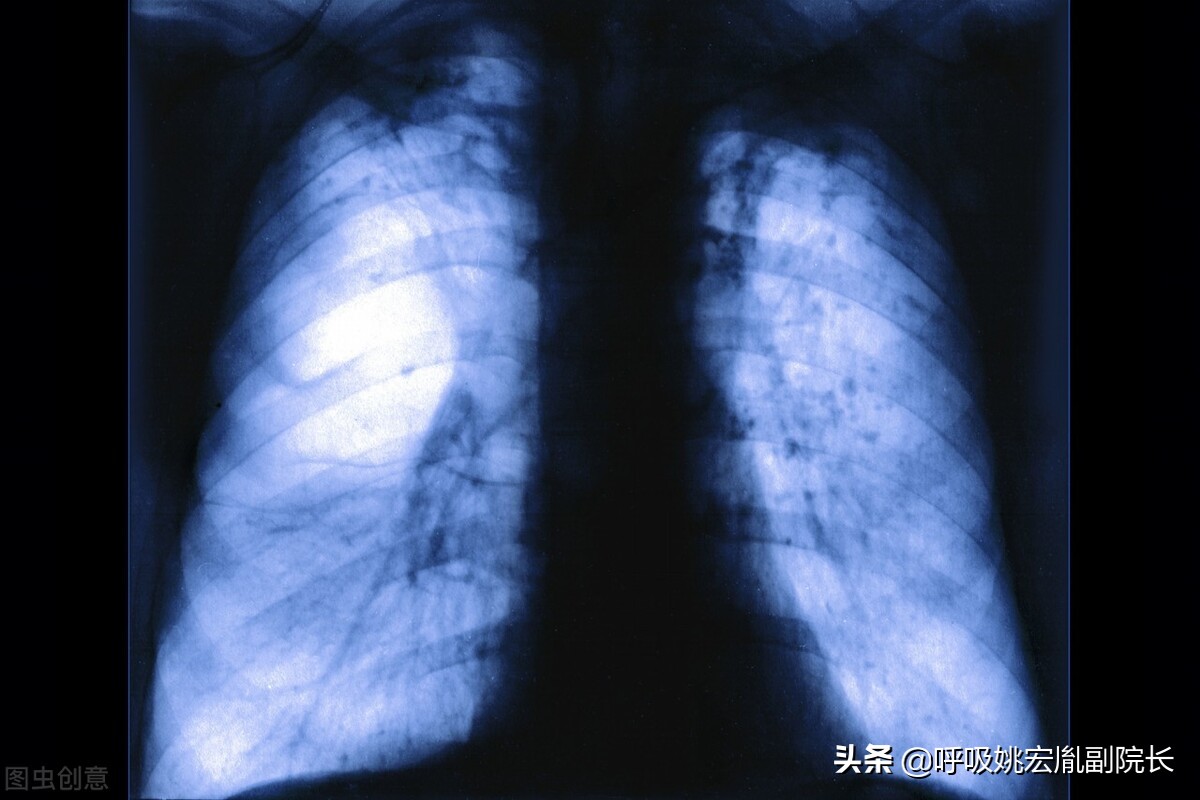

肺气肿:

肺气肿是指终末细支气管远端的气道弹性减退,过度膨胀、充气和肺容积增大或同时伴有气道壁破坏的病理状态。按其发病原因肺气肿有如下几种类型:老年性肺气肿、代偿性肺气肿、间质性肺气肿、灶性肺气肿、旁间隔性肺气肿、

阻塞性肺气肿

。